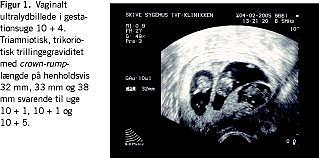

En vaginalskanning i uge 7+0 viste overraskende triamniotisk, trikoriotisk trillingegraviditet. Fostrene målte henholdsvis 8,4, 7,5 og 4 mm, svarende til gestationsuge 7+0, 6+5 og 6+1. Efterfølgende skanninger viste normal tilvækst, og parret afstod fra fosterreduktion (Figur 1).